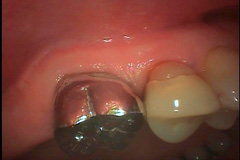

歯根が2つに割れています。写真の縦方向に割れた線が入っています。通常は抜歯が唯一の治療方法になります。

歯は抜かずに、口の中で破折した部分を清掃して、割れを接着したところです。歯を抜いたり、歯肉を切開したりはしていません。見えない部分かつ水分の多い条件で清掃と接着を行いますので熟練の技が必要です。

接着後しばらく経過観察をして、コア(かぶせの土台になる部分)を作りました。

銀歯をかぶせました。原稿を書いている時点で5年弱経過して、問題なく機能しています。